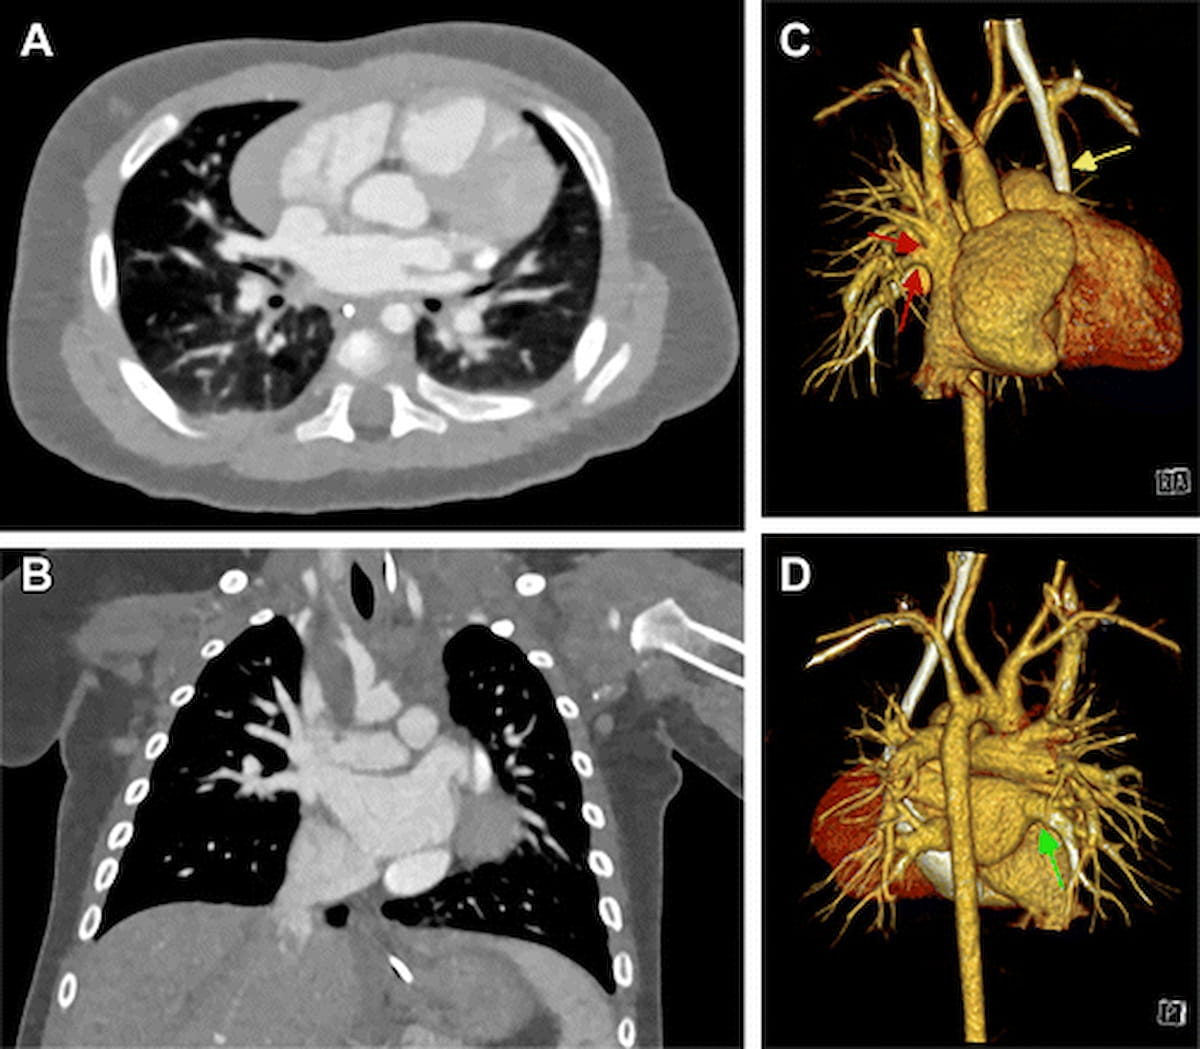

Здесь можно увидеть изображения компьютерной томографии (КТ) с подсчетом фотонов сердца и последующие передние и задние трехмерные реконструкции для 174-дневного младенца мужского пола с врожденным пороком сердца. (Изображения предоставлены Радиологией .)